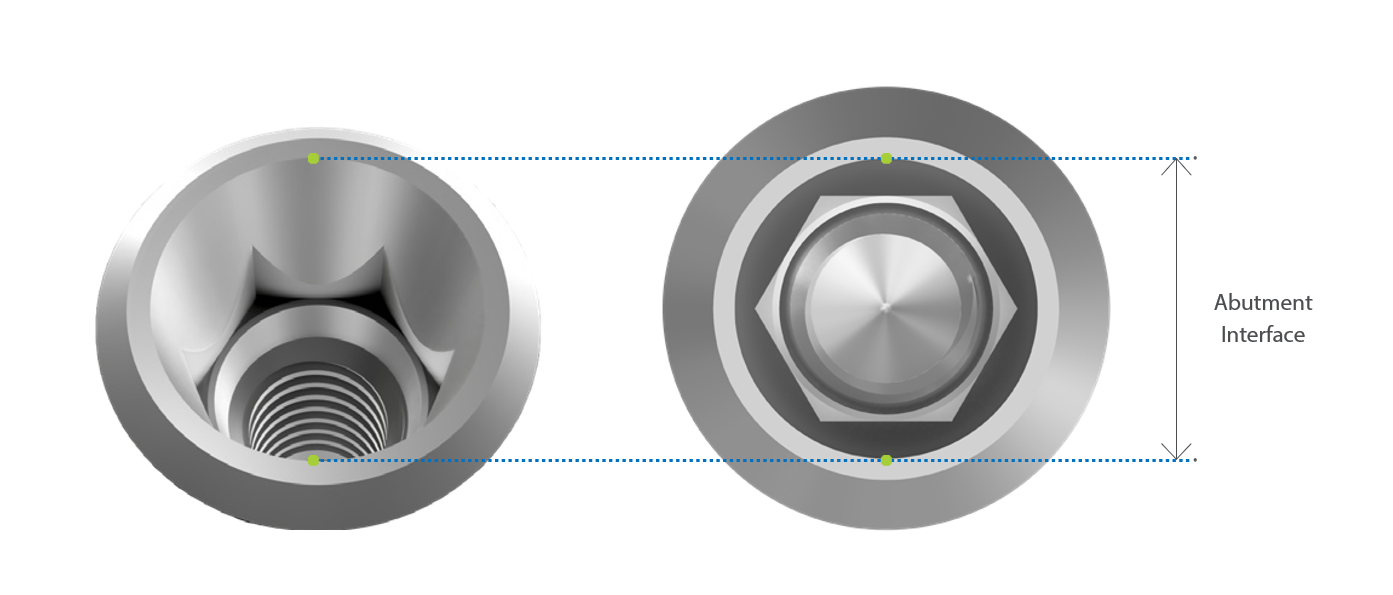

Conical Hex Connection

The tapered conical hex connection provides excellent stability, while the deep prosthetic design distributes loading forces broadly into the implant.

This enhances connection stability, minimizes micro-movement, and helps reduce long-term marginal bone loss.